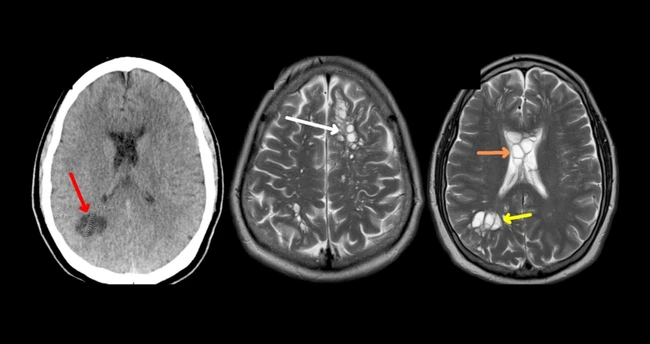

Scanările CT au evidențiat numeroase focare chistice FOTO American Journal of Case Reports/ NBC

Prin urmare, pacientul a fost internat în spital pentru testare. Scanările CT au evidențiat numeroase focare chistice, care sunt saci umpluți cu lichid în creier. Testele de anticorpi pentru chistul cisticercozei au fost pozitive, iar bărbatul a fost diagnosticat cu neurocisticercoză, se arată în studiu.